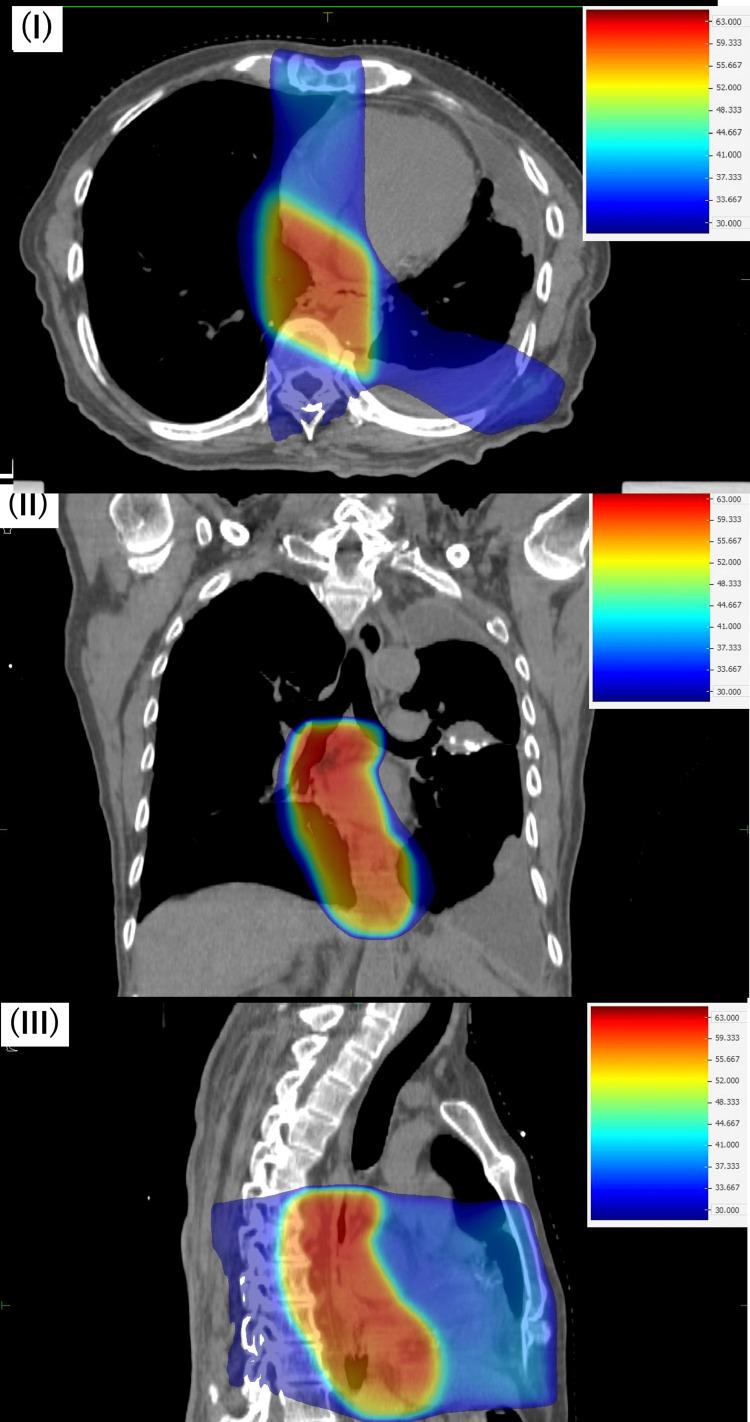

Thoracic re-irradiation has a high risk of severe adverse events, and re-irradiation with curative intent has rarely been performed. However, in recent years, with the introduction of intensity-modulated radiation therapy (IMRT) and stereotactic body radiation therapy, it has become possible to deliver high doses to the target lesions while minimizing the doses to surrounding tissues. The patient in this case had a history of definitive radiation therapy for esophageal cancer. The patient developed new lung cancer, which was treated by re-irradiation. We created a radiation treatment plan using IMRT. This allowed us to reduce the dose to organs at risk and deliver a higher dose to the cancer, increasing the potential for cure. The patient has not experienced any severe late adverse events as of three years and six months after treatment. Additionally, the treatment has been sufficiently effective, and the patient remains recurrence-free. To confirm the feasibility of the IMRT plan, we also created a radiation treatment plan using three-dimensional conformal radiation therapy (3D-CRT) and compared it with the IMRT plan. Compared with 3D-CRT, the IMRT plan was able to reduce the dose to organs at risk and meet the dose constraints indicated in multiple studies. The possibility of adverse events such as bronchial hemorrhage, esophageal hemorrhage, bronchial fistula, radiation pneumonitis, esophageal fistula, and pericarditis was significantly reduced.

胸部再程放疗有发生严重不良事件的高风险,且很少进行有治愈意图的再程放疗。然而,近年来,随着调强放射治疗(IMRT)和立体定向体部放疗的引入,在将周围组织剂量降至最低的同时向靶病变给予高剂量已成为可能。该病例患者有食管癌根治性放疗史。患者新发肺癌,接受了再程放疗。我们使用IMRT制定了放射治疗计划。这使我们能够降低危及器官的剂量,并向癌症给予更高剂量,增加治愈的可能性。截至治疗后三年零六个月,患者未出现任何严重的晚期不良事件。此外,治疗效果充分,患者仍无复发。为确认IMRT计划的可行性,我们还使用三维适形放疗(3D-CRT)制定了放射治疗计划,并将其与IMRT计划进行比较。与3D-CRT相比,IMRT计划能够降低危及器官的剂量,并满足多项研究中指出的剂量限制。支气管出血、食管出血、支气管瘘、放射性肺炎、食管瘘和心包炎等不良事件的可能性显著降低。